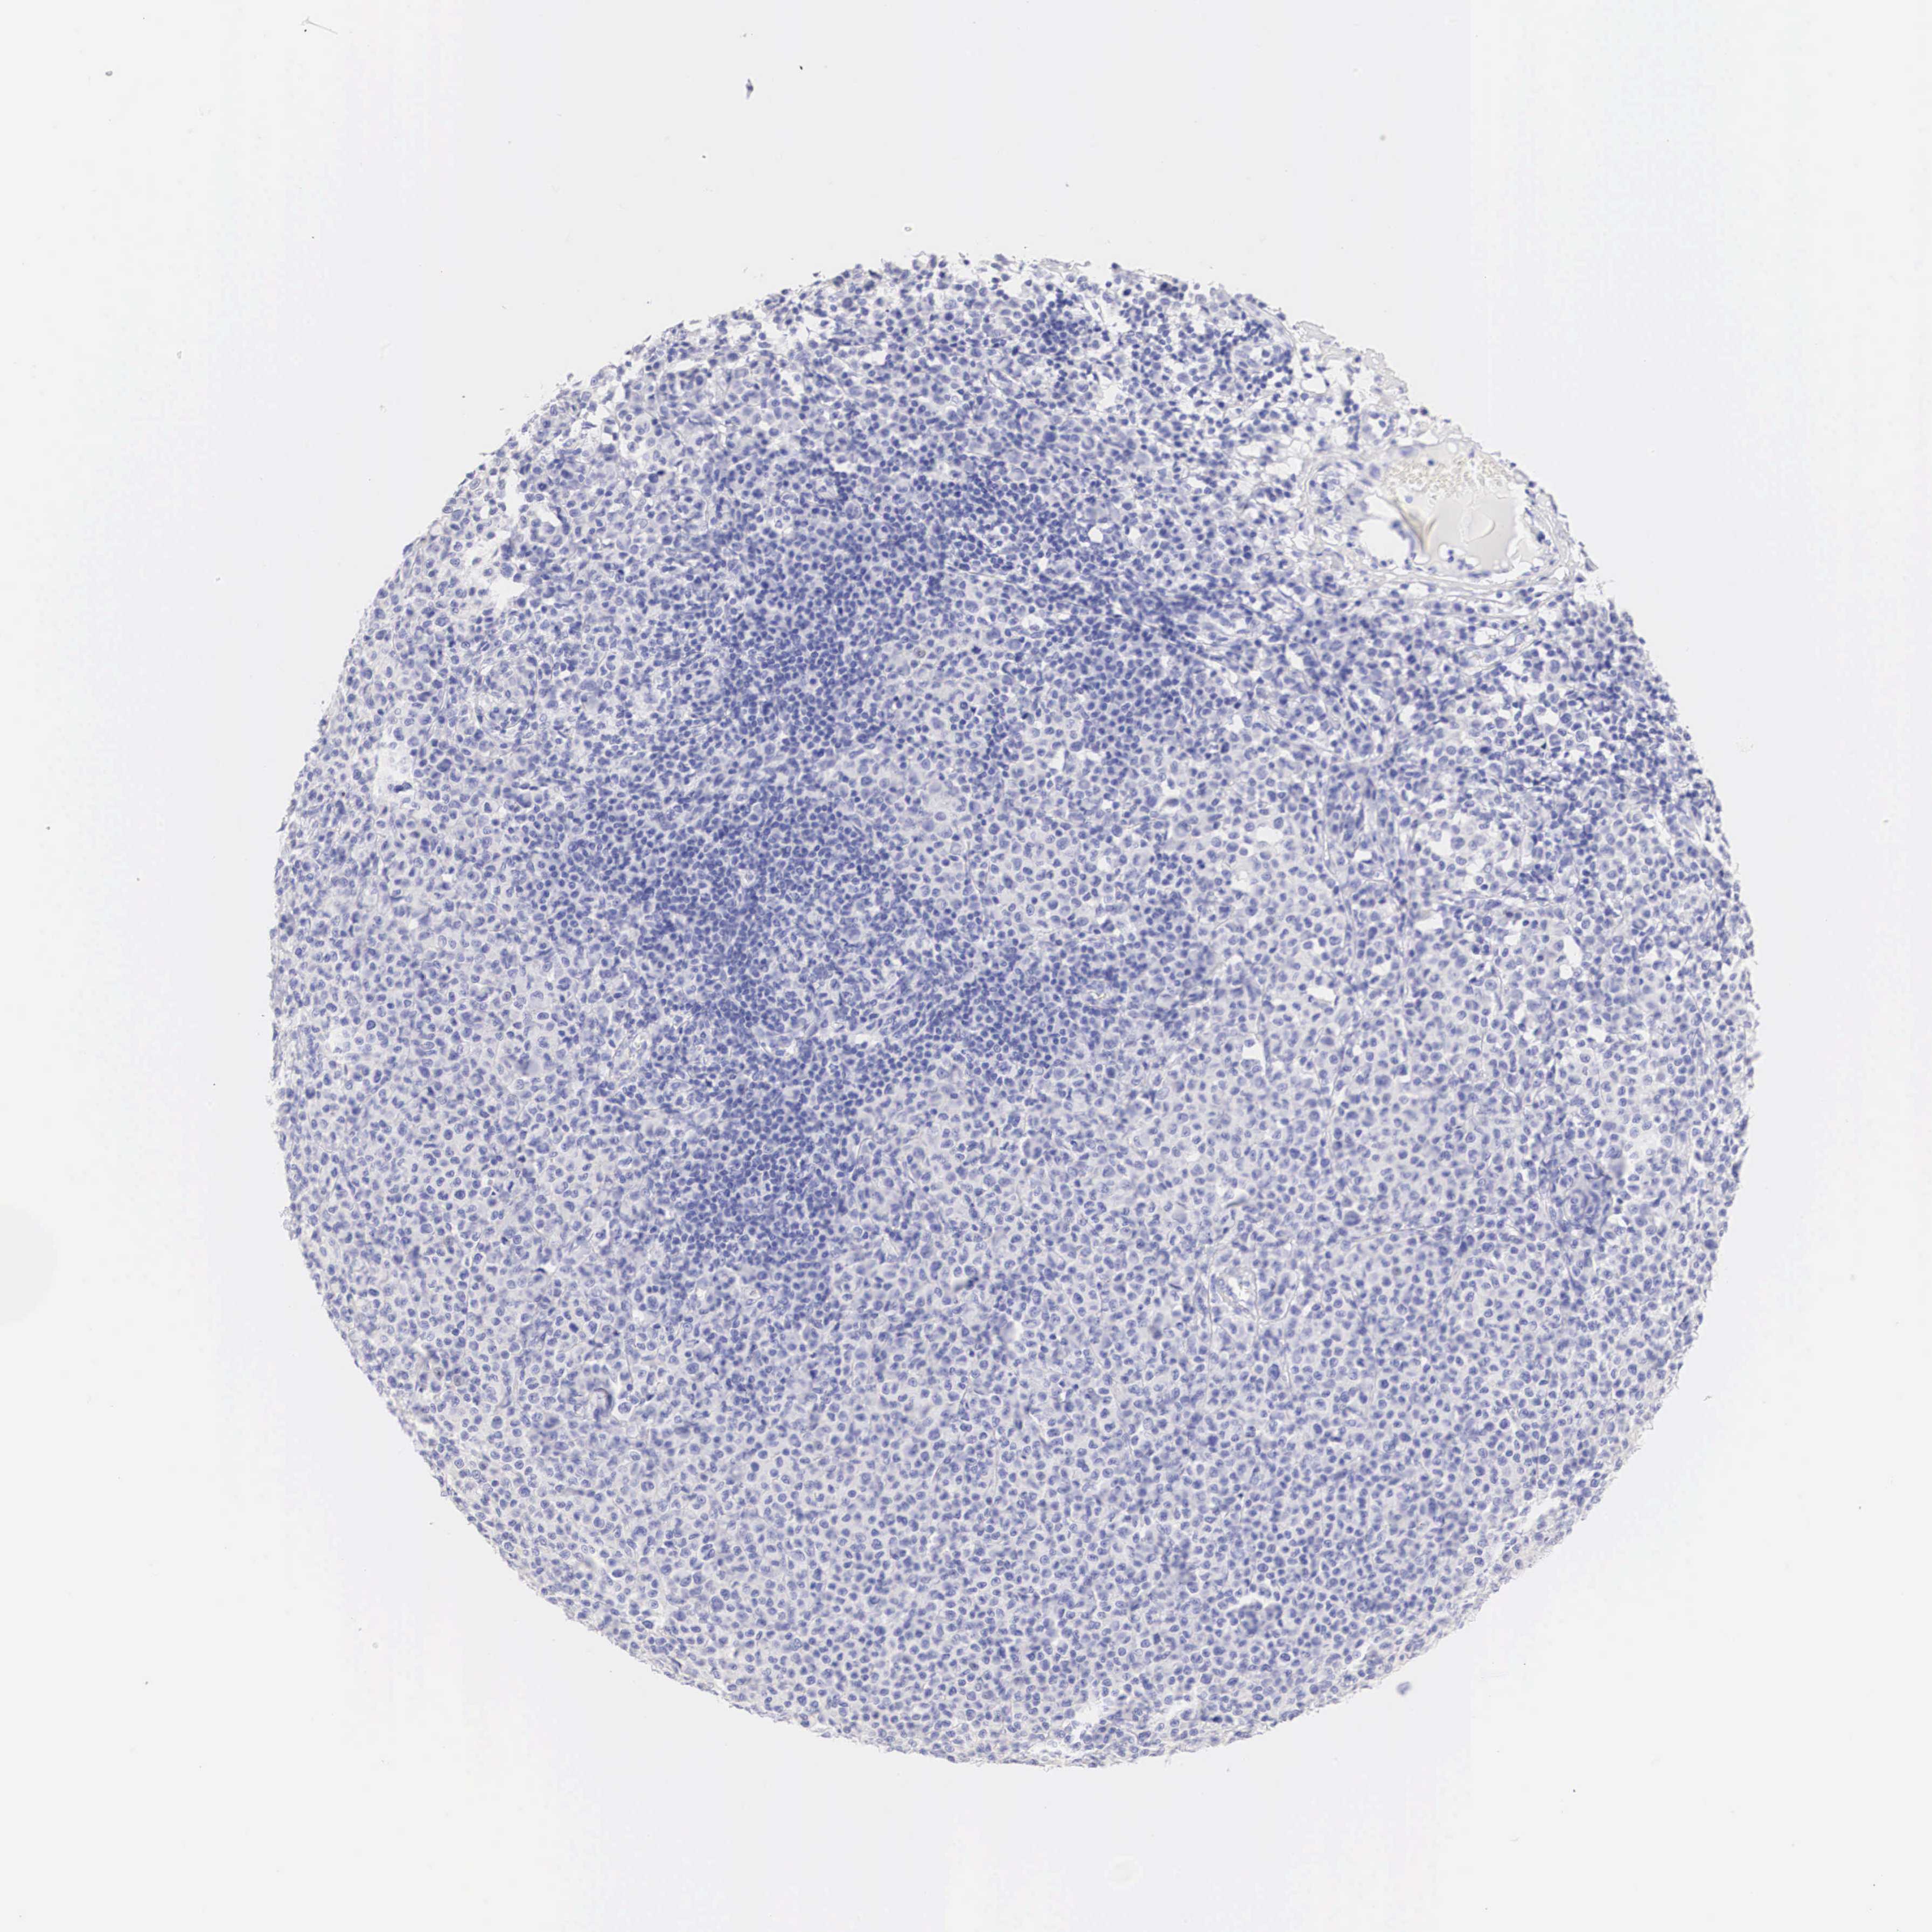

MELANOMA - Protein expressioni

A mouse-over function shows sample information and annotation data. Click on an image to view it in a full screen mode. Samples can be filtered based on level of antibody staining by selecting one or several of the following categories: high, medium, low and not detected. The assay and annotation is described here.

Note that samples used for immunohistochemistry by the Human Protein Atlas do not correspond to samples in the TCGA dataset.

Antibody stainingi

Antibody staining in the annotated cell types in the current human tissue is reported as not detected, low, medium, or high, based on conventional immunohistochemistry profiling in selected tissues. This score is based on the combination of the staining intensity and fraction of stained cells.

Each image is clickable and will lead to virtual microscopy that enables deeper exploration of all samples and also displays staining intensity scores, fraction scores and subcellular localization as well as patient and tissue information for each sample.

Antibody HPA001383

Antibody CAB000043

Antibody CAB020416

Antibody CAB062555

Malignant melanoma, NOS

Malignant melanoma, Metastatic site